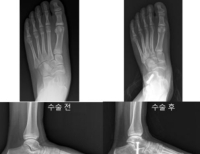

- 봉합 불가능한 회전근개 파열, 수술법에 따라 효과·합병증 위험 크게 달라

- 경기도에 거주하는 김 모씨(69세)는 수년 전부터 지속된 어깨통증으로 일상생활에 큰 불편을 겪었다. 팔을 들어 올리거나 뒤로 돌릴 때마다 심한 통증을 호소...

- 2025-09-19